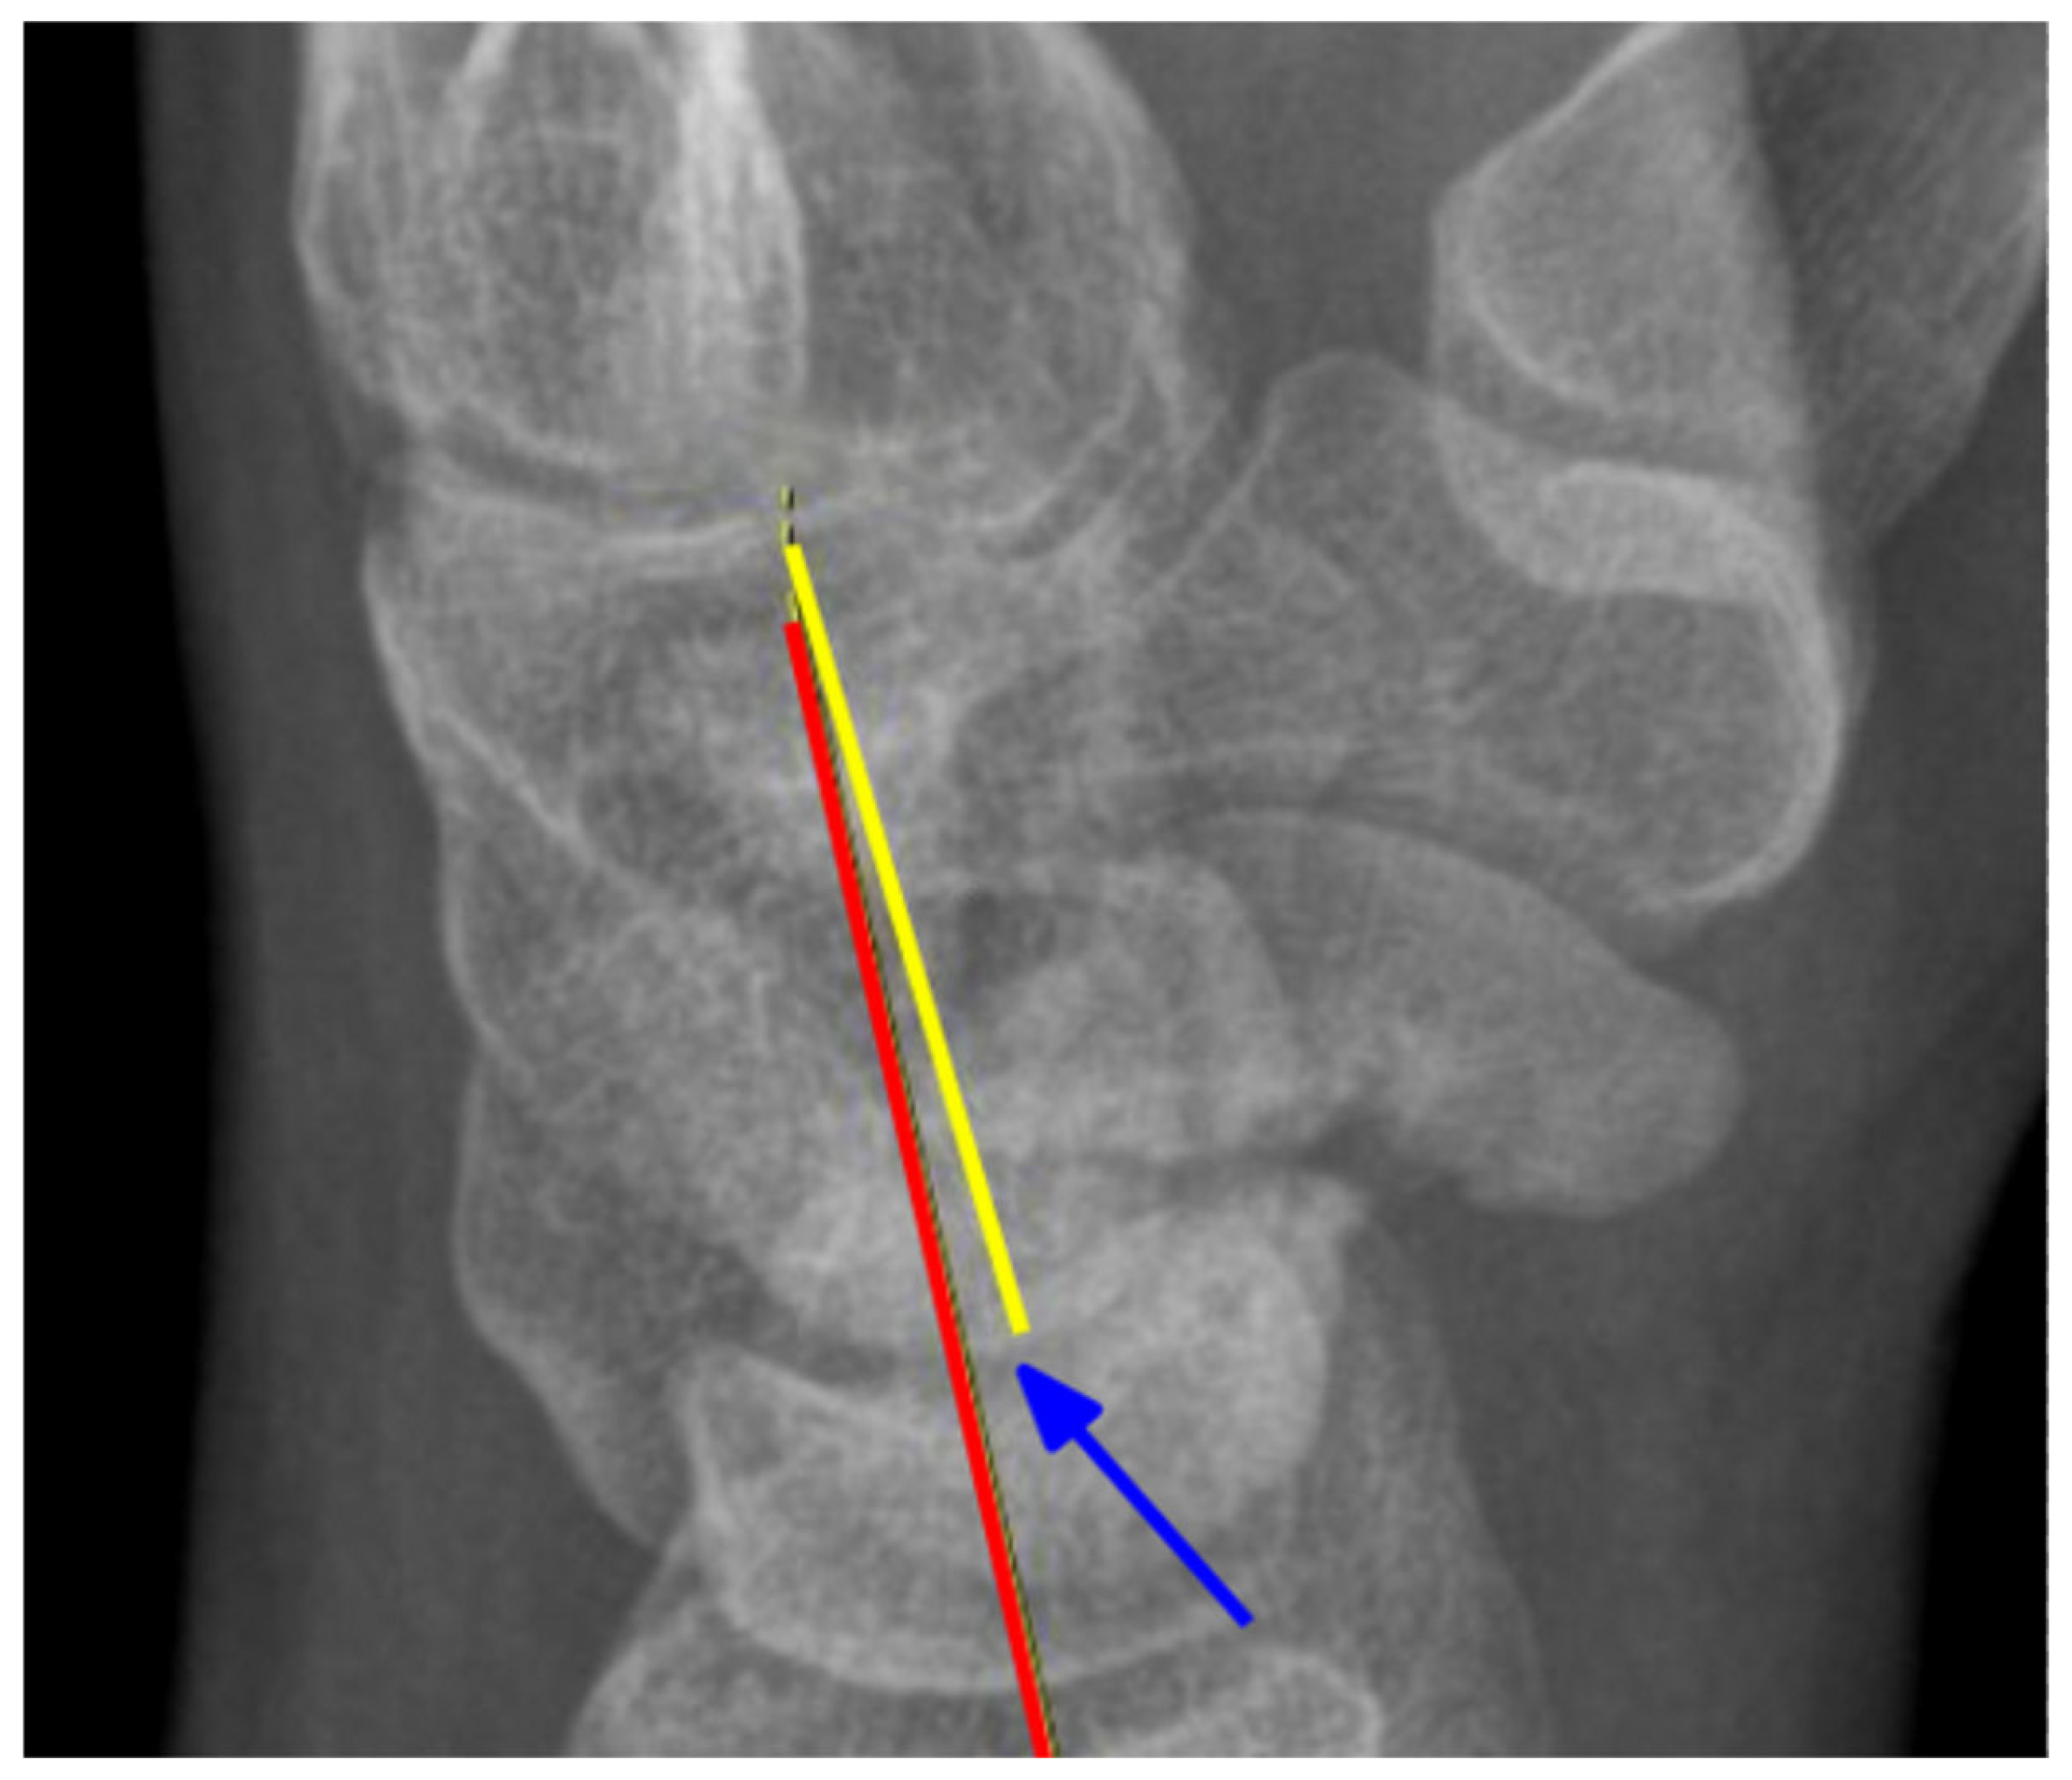

2.2. Radiological Assessment

| CLA | Capitolunate angle |

| SLA | Scapholunate angle |

| SCA | Scaphocapitate angle |